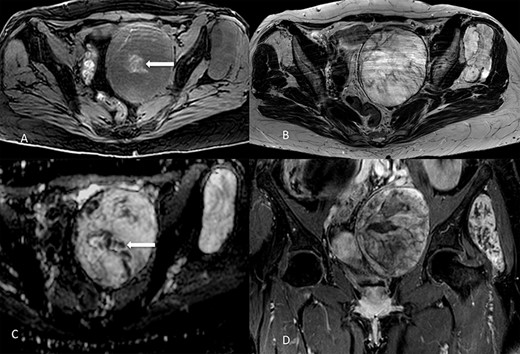

On 1.5T MR (Fig. 2), masses were slight hypointense as compared to muscle on T1-weighted imaging, with sparse hyperintense foci suggesting the presence of hemorrhage, especially in the pelvic one. Signal intensity was predominantly slightly higher than fat on T2-weighted images, with internal low-signal septa, showing restricted diffusion and minimal contrast-enhancement. The hyperintense component was characterized by inhomogeneous contrast enhancement. Of note, there was some asymmetry between the lesions, with the pelvic one showing more inhomogeneity on T2-weighted imaging and less intense contrast-enhancement as compared to the extrapelvic one. Overall, MR findings were in line with previously reported findings [5]. At radiological scans, no distant metastases were documented in the liver or lungs.

Lesions appearance on MR imaging. On transverse fat-saturated volumetric gradient echo T1-weighted imaging (A) both masses appeared slightly hypointense compared to muscle, with hyperintense areas in the larger one (arrow) suggesting the presence of haemorrhagic foci. Lesions were hyperintense on transverse turbo spin-echo T2-weighted imaging (B), in line with the presence of myxoid content, showing inhomogeneous appearance due to low-signal septa showing restricted diffusion on the apparent diffusion coefficient map (arrow in C). Contrast enhancement was inhomogeneous, as shown in the coronal fat-saturated post-contrast image (D). Masses showed well-defined margins, with no invasion of the adjacent structures.